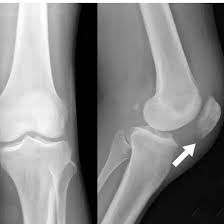

X-ray Knee AP/LAT View

The X-Ray Knee AP (Anteroposterior) and LAT (Lateral) View is a diagnostic imaging process that provides detailed views of the knee joint, bones, cartilage, and surrounding structures. The AP view displays the knee from the front, but the lateral view shows it from the side, providing for a more thorough assessment of knee health.

An X-ray Knee AP/LAT View scan captures two key angles of the knee — AP (Anteroposterior) for a front view and LAT (Lateral) for a side view. It helps assess bones, joints, and soft tissues to detect injuries or abnormalities.

An X-ray Knee AP/LAT View can detect fractures, arthritis, joint dislocations, bone deformities, and signs of swelling or ligament damage. It’s commonly used to evaluate knee pain, injuries, and joint conditions.